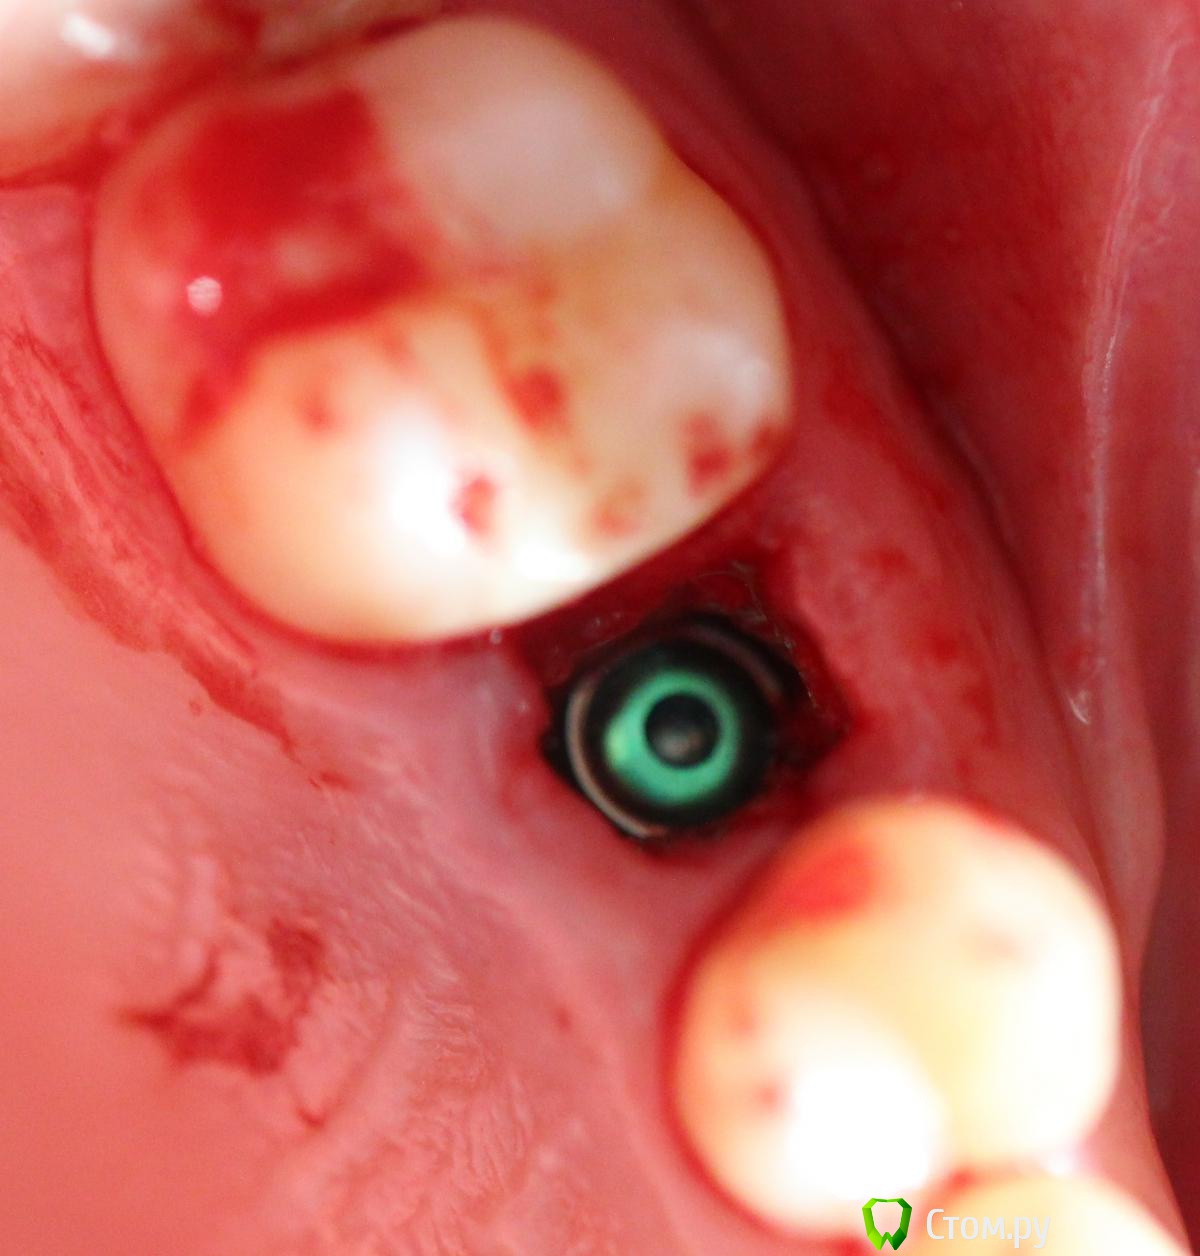

Andex Опубликовано 6 июля, 2014 Поделиться Опубликовано 6 июля, 2014 Всем привет! Вдохновленный великолепными кейсами докторов с форума, выкладываю свой случай. Коментарии и критика(особенно) приветствуются! Пациент обратился с переломом корня Я решил пойти по простому пути, тк мукогингивальными трансплантатами не владею в должном качестве - просто сошлифовал корень на 1,5 мм ниже прикрепления, и подождал 2 недели - знаю, что маловато, но руки чесались сделать операцию. Вид через 2 недели Удаляем корень и ставим имплант Устанавливаем заглушку Мобилизируем лоскут с неба и ушиваемся, нитка - моносин 5.0 Виновник торжества - слегка в стиле гиперреализма Снимки до и после имплантации - визиограф не информативен в полной мере - вживую имплант заглублен мах на 2 мм 4 Ссылка на комментарий

Andex Опубликовано 6 июля, 2014 Автор Поделиться Опубликовано 6 июля, 2014 что за винт?osstem ts IV d=4.5m L=10mm Ссылка на комментарий

Andex Опубликовано 6 июля, 2014 Автор Поделиться Опубликовано 6 июля, 2014 и кроме мезио-достального расстояниявинт - семадоз r-line? (3.25) что с вестибулярной кортикальной пластинкой? (как правило, при таких переломах она отсутствует) Винт - osstem d4.5 - L10.0.Вестибулярно кортикальной нет примерно на 2 мм в области шейки зуба, далее апикальнее она впорядке, поэтому ришлось заглублять на 2 мм(фотки что то перестали загружаться) - и получилось, что винт встал вровень с кортикальной весибулярно и на 2мм субкрестально с небной стороны.- насколько это критично? Сошлифовать 2 небных мм рука не поднялась Ссылка на комментарий